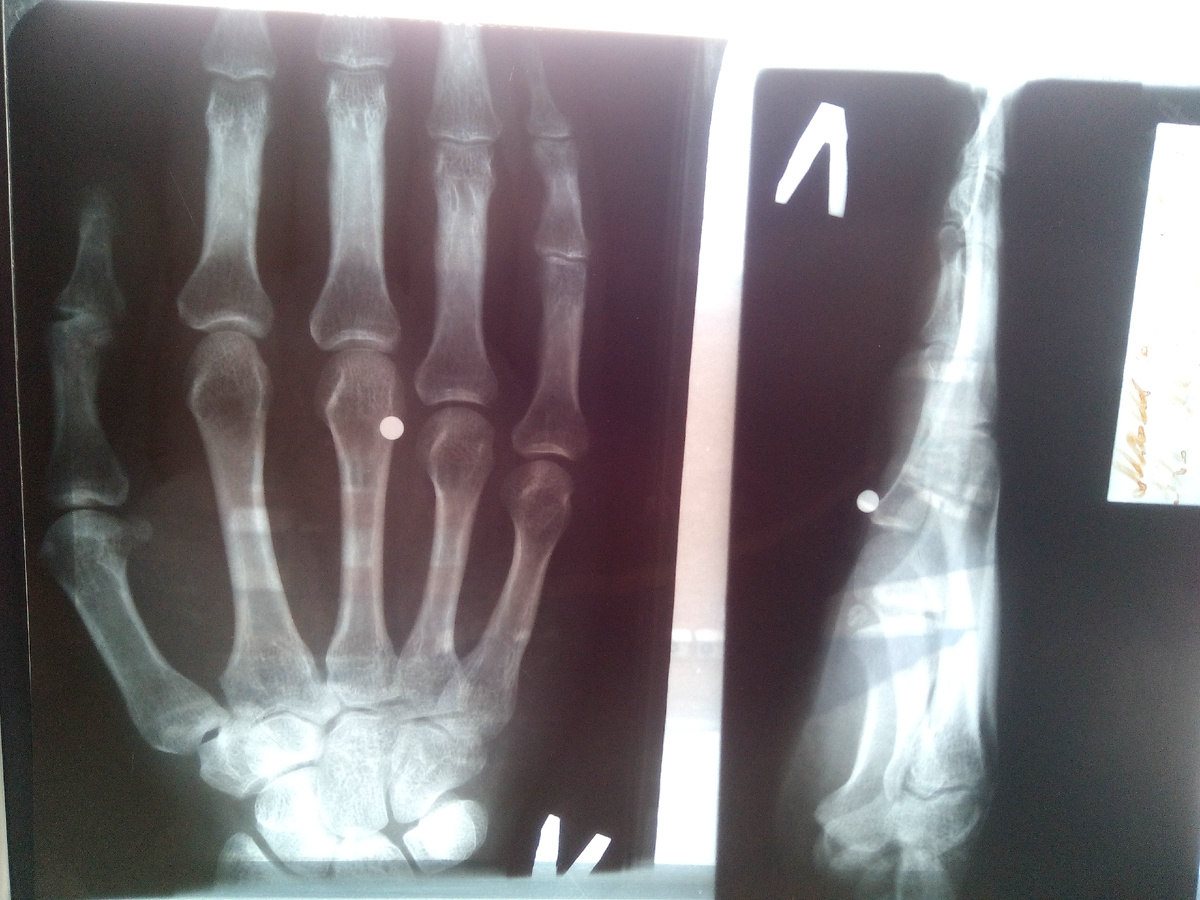

в руке дыра, кровь, боль - но тупая, под алконаркозом все таки), ладонь переворачиваю - выходного отверстия нет, спиртом смочили и спать. На утро в дежурную травматологию еду (рассказываю что да как), врач осматривает, делает снимок, ставят местный наркоз, разрезают рану, ковыряется там 10минут и так и эдак но без результатно. Мужина хирург со словами я тебя все равно достану еще 5 минут копается в моей ладони ему уже самому интересно) где это ОНО (инородное тело) там спряталось.

А ВОТ и ОНО - пулька медная 1шт d4мм

Встречает меня седой пожилой и опытный хирург, посмотрев снимок и выслушав мой рассказ о предыдущим "Металлоискателе" он делает вывод и говорит что "оно" находится за сухожилием упершись в кость, т.к. сухожилие эластичные они ее через себя пропустили без повреждений (вот почему ее не нашел предыдущий), а достать ее не возможно без операции и разреза этих сухожилий а потом еще и сшивания. а это не очень приятная процедура.